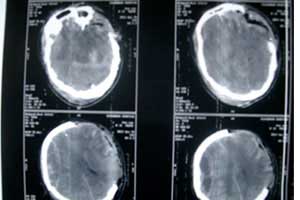

颅骨损伤是指头部骨骼中的一块或多块发生部分或完全断裂的疾病,多由于钝性冲击引起。

颅骨结构改变大多不需要特殊处理,但如果伴有受力点附近的颅骨内的组织结构损伤,如血管破裂、脑或颅神经损伤,脑膜撕裂等,则需要及时处理,否则可引起颅内血肿、神经功能受损、颅内感染及脑脊液漏等严重并发症,影响预后。